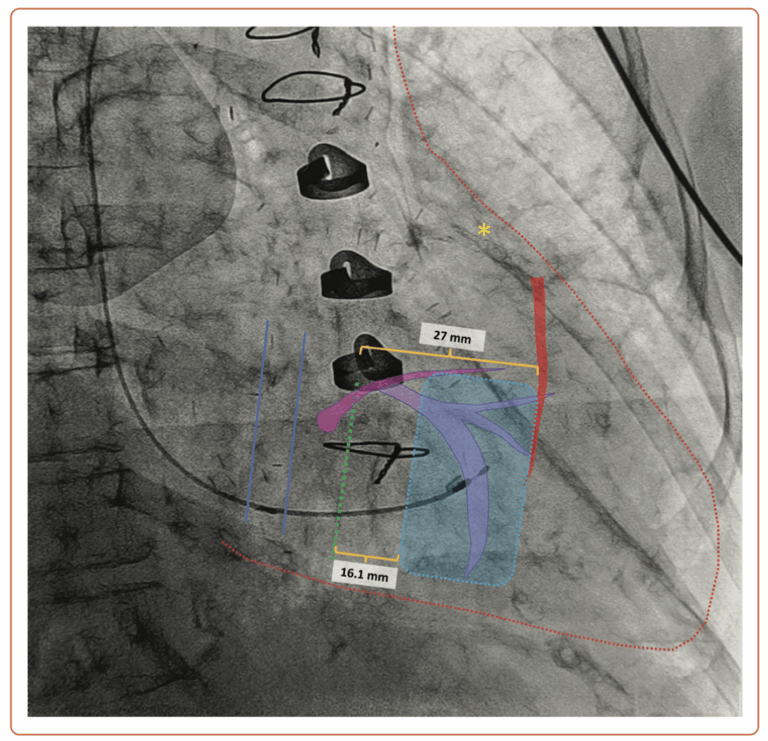

Think of the heart as a tricky neighborhood: the coronary sinus (between the blue lines) is like a clear alleyway, while the tricuspid valve (green dashed line) sits just slightly next door. In this patient, we’ve spotted the left anterior descending artery (marked by the yellow star) with its first septal perforator (highlighted in red) branching off about 27 mm away from the tricuspid valve’s doorstep. To keep things friendly and not make the valve leak worse, the pacing lead needs its own ‘personal space’—at least 16 mm away. That means the ideal spot (the safe zone, marked by the dashed blue area) for placing the lead is comfortably between 16 and 27 mm from the valve. No awkward neighbors here!